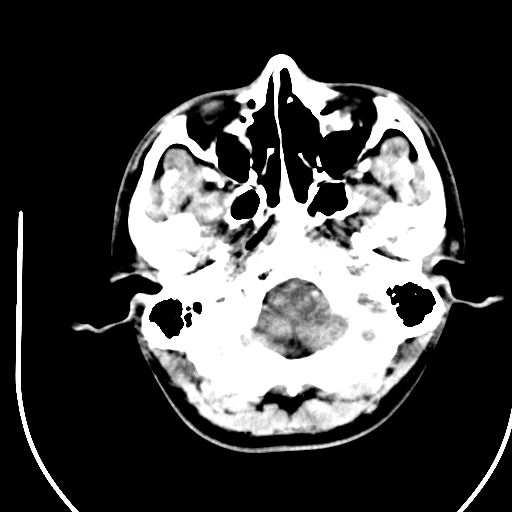

标题: CT28158:男,27Y。头痛数月,左顶叶血管瘤。 [打印本页]

标题: CT28158:男,27Y。头痛数月,左顶叶血管瘤。

海绵状血管瘤

考虑左顶叶海绵状血管瘤,建议mr检查。

左侧额叶海绵状血管瘤可能性大;建议行mri检查。

考虑血管畸形,因其周可见水肿,不除外感染性病灶。建议mri检查。